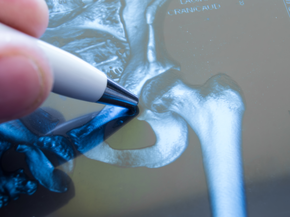

Hip Cartilage Repair

Removes unstable cartilage, while microfracture helps restore the joint with scar tissue that behaves like cartilage.

First, your surgeon will obtain x-rays to evaluate your joint and determine whether or not you're a candidate for cartilage restoration surgery. Advanced imaging, such as an MRI, is usually necessary to assess cartilage defects and develop a treatment plan.